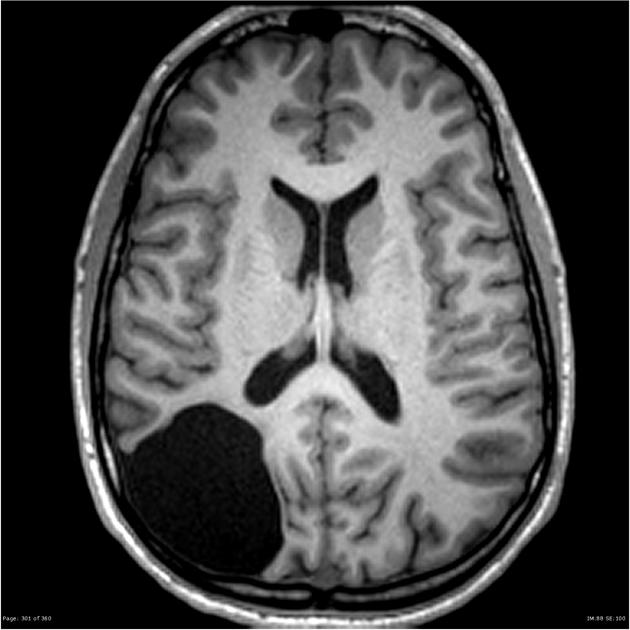

Rỗ não (Porencephaly) là một rối loạn hiếm gặp thường được chẩn đoán trước khi sinh hoặc trong thời kỳ sơ sinh. Tổn thương ở bán cầu não của trẻ có thể xảy ra trong thời kỳ mang thai hoặc ngay sau khi sinh. Tổn thương này dẫn đến sự phát triển của các khoang chứa đầy dịch, được gọi là nang, trong não của trẻ.

Rỗ não (Porencephaly) có thể được chẩn đoán trong hoặc sau khi mang thai.

- Trong thai kỳ, nó được chẩn đoán thông qua một trong hai loại hình ảnh thần kinh. Lựa chọn đầu tiên là siêu âm. Lựa chọn thứ hai là chụp cộng hưởng từ (MRI). Hình ảnh thần kinh có thể quan sát não bộ đang phát triển của thai nhi trong bụng mẹ.